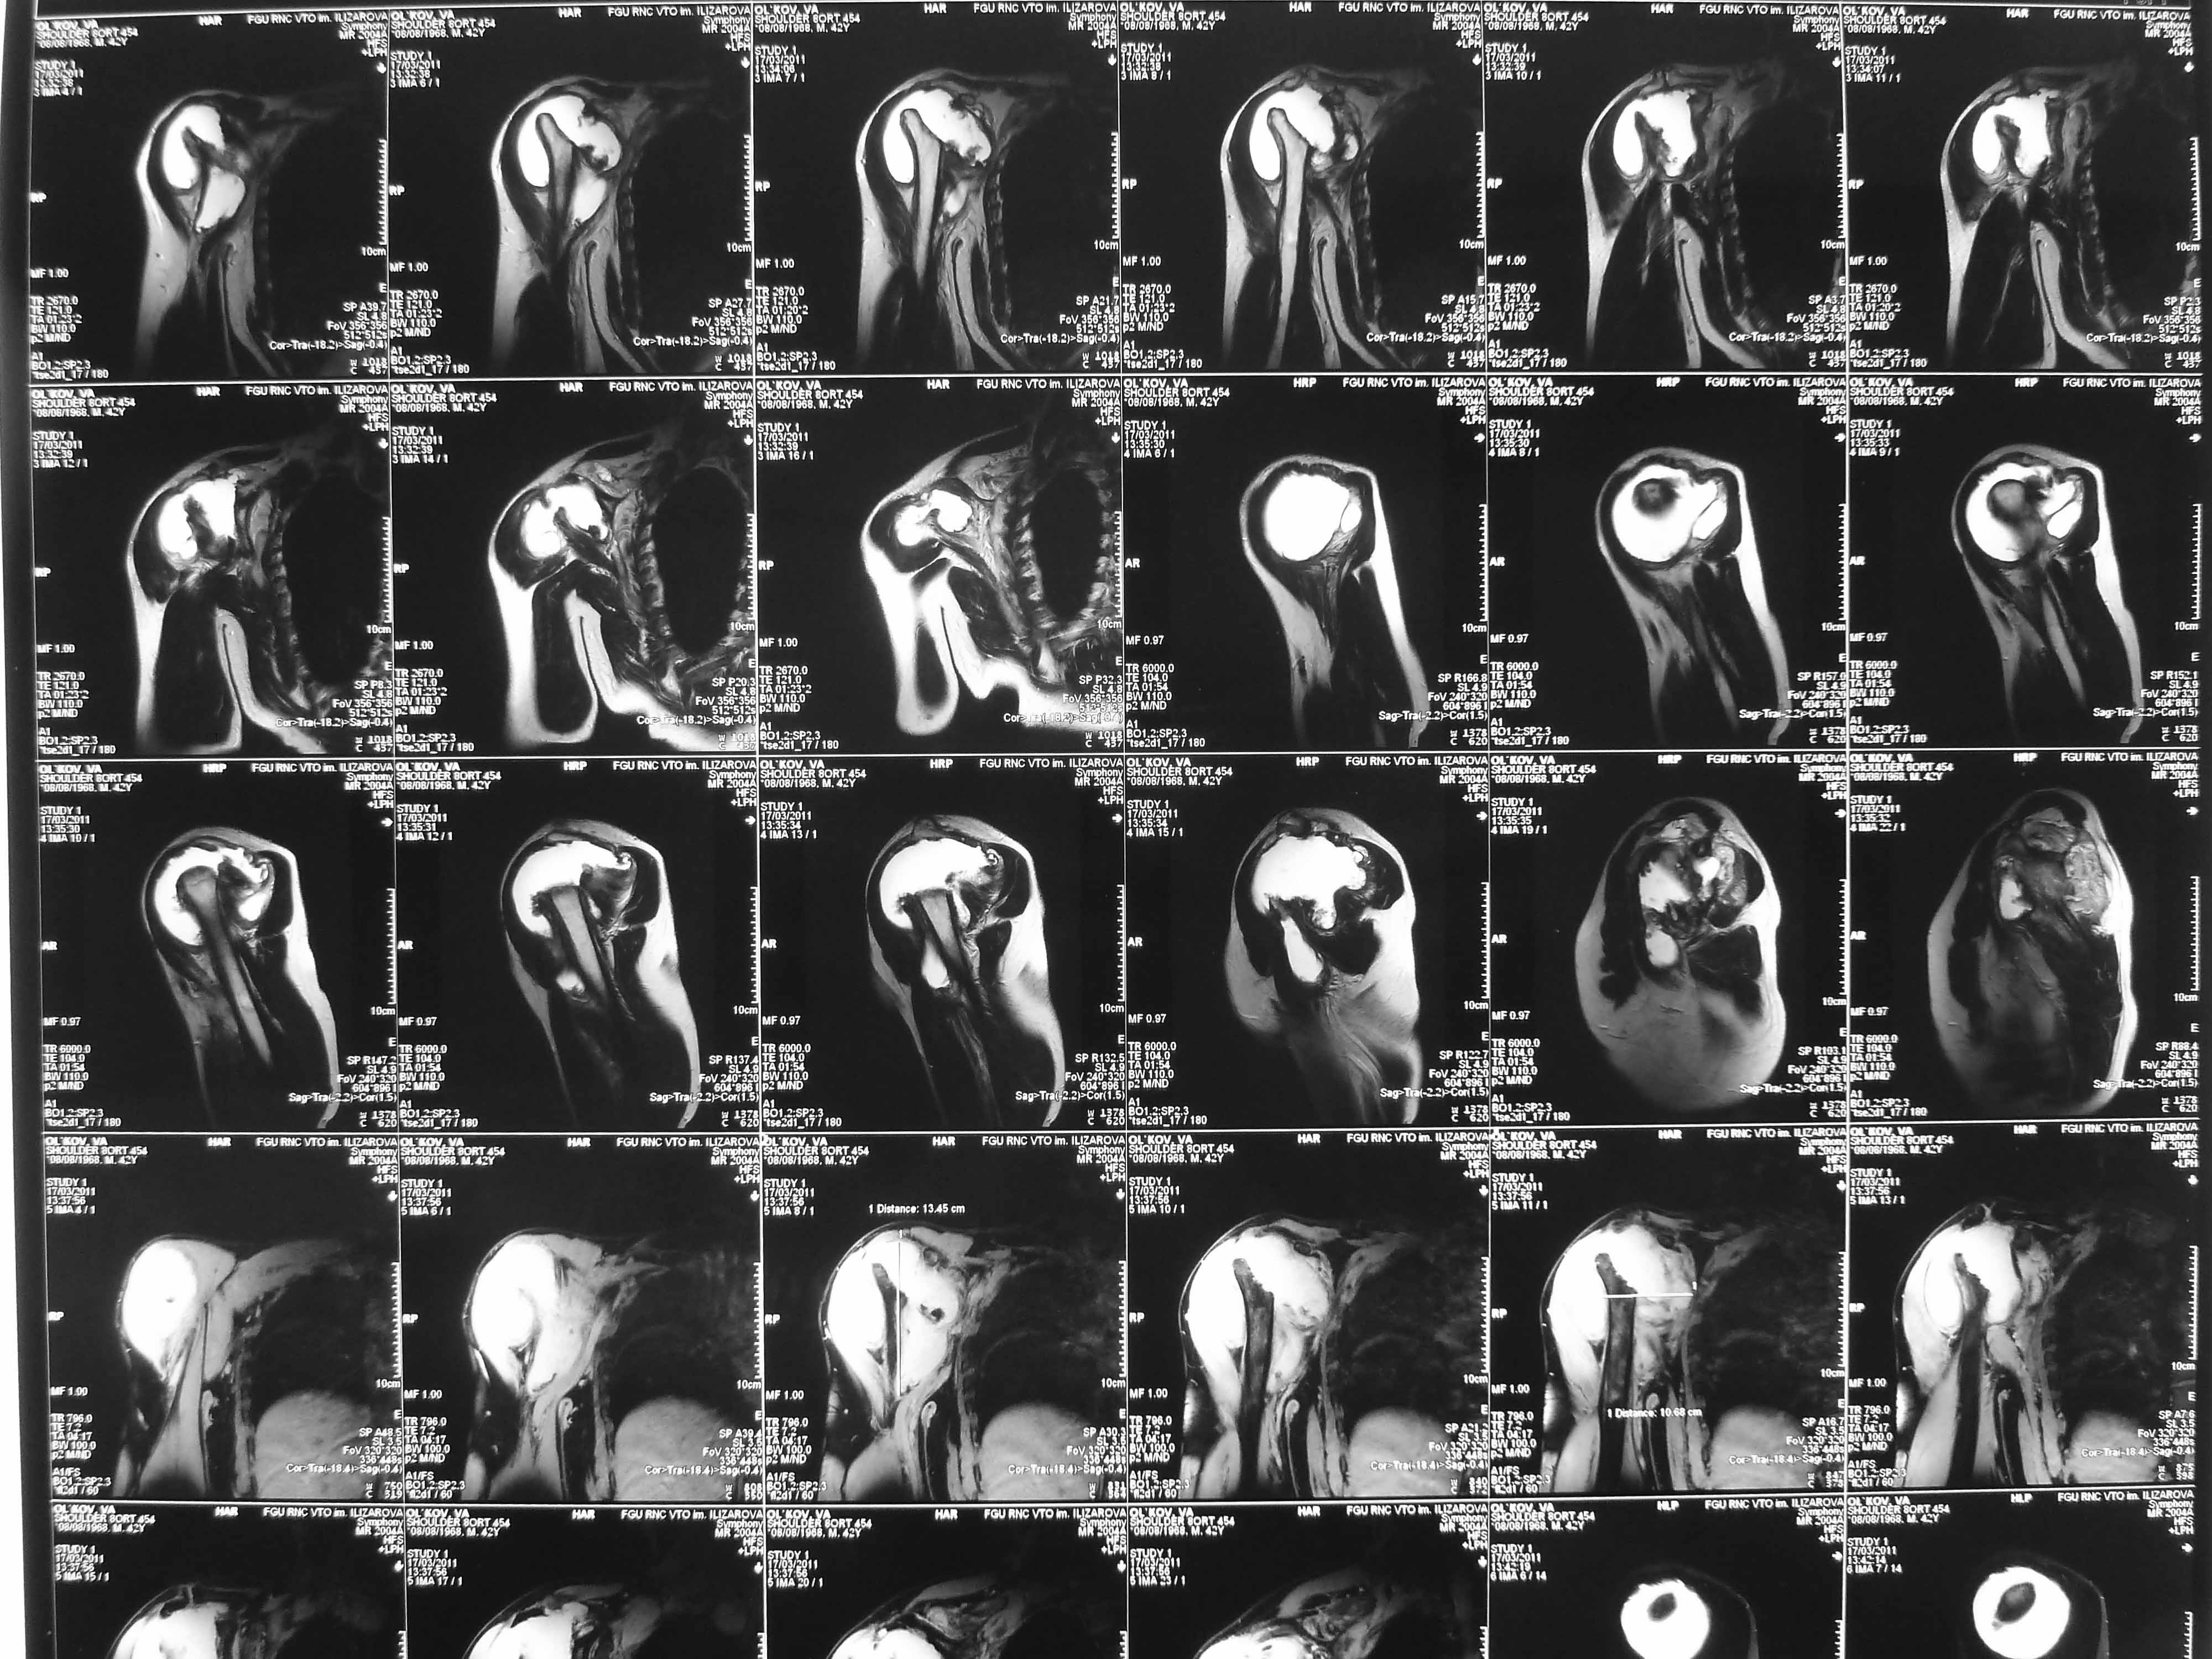

Поэтому желательно выставить все рентгенологические и данные МРТ для сравнения со снимками из статьи.

Думаю, коллеги будут не против увидеть рентген.

Извиняюсь, что-то фотографии сразу не прошли. сейчас исправимся.